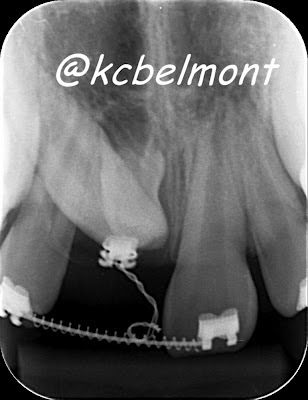

![]()  |

| radiografia periapical (CIR - Centro da Imagem Radiológica) |

A solução encontrada pelo dentista deste paciente foi o tracionamento, através da Ortodontia e para acompanhar solicitou uma radiografia panorâmica e uma periapical da região.